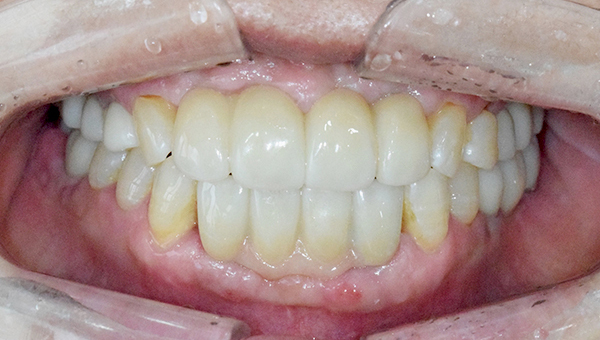

강*란 임플란트 시술 사례

전체 임플란트

2025.08.19

치료 후